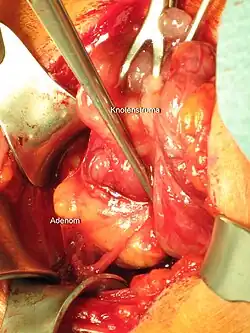

Die Therapie des primären Hyperparathyreoidismus erfolgt durch operative Entfernung des Nebenschilddrüsen-Adenoms. Ist eine Operation nicht möglich oder wird diese nicht gewünscht, kann bei geringgradig erhöhtem Serum-Calcium der Krankheitsverlauf durch regelmäßige Kontrollen von Parathormon und Calcium beobachtet werden. Bei stark erhöhtem Calcium kann die Bildung von Parathormon durch das Medikament Cinacalcet gehemmt werden.

Chirurgische Therapie

Die chirurgische Entfernung des (oder aller) vergrößerten Epithelkörperchens, führt im Vergleich zur Verlaufsbeobachtung zu einer Verbesserung von Knochendichte und Lebensqualität[62] sowie zu einer Verminderung von Knochenbrüchen, insbesondere von Schenkelhalsfrakturen.[63] In der Mehrzahl der asymptomatischen Patienten finden sich aber auch bei langer Verlaufsbeobachtung keine Hinweise auf ein Fortschreiten der Erkrankung wie Abnahme von Knochendichte, Anstieg von Calcium und Parathormon oder Auftreten von Nierensteinen.